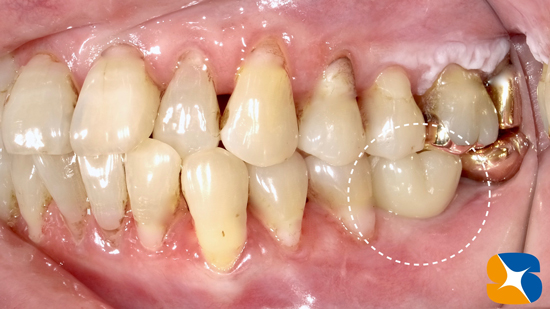

これは、骨の造成施術を終えて5ヶ月後の歯茎の状態です。ほっぺから続く薄い粘膜が、インプラント移植予定の部分にまで広がっています。

完成したインプラントの周囲に、ほっぺたから続く薄い粘膜で囲まれることは良いとはされていませんが‥。